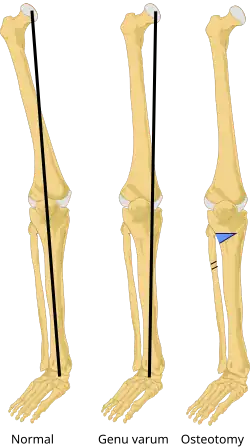

On projectional radiography, the degree of varus or valgus deformity can be quantified by the hip-knee-ankle angle,[9] which is an angle between the femoral mechanical axis and the center of the ankle joint.[10] It is normally between 1.0° and 1.5° of varus in adults.[11] Normal ranges are different in children.[12]

Generally, no treatment is required for idiopathic presentation as it is a normal anatomical variant in young children. Treatment is indicated when it persists beyond 3+1⁄2 years old. In the case of unilateral presentation or progressive worsening of the curvature, when caused by rickets, the most important thing is to treat the constitutional disease, at the same time instructing the care-giver never to place the child on their feet. In many cases, this is quite sufficient in itself to effect a cure, but matters can be hastened somewhat by applying splints. When the deformity arises in older patients, either from trauma or occupation, the only permanent treatment is surgery, but orthopaedic bracing can provide relief.

Treatment for children with Blount's disease is typically braces but surgery may also be necessary. In children guided growth surgery is used to gradually correct/straighten the bow legs.[13] For teenagers osteotomy or bone cutting is often used to correct the bone deformity. The operation consists of removing a piece of tibia, breaking the fibula and straightening out the bone; there is also a choice of elongating the legs. If not treated early enough, the condition worsens quickly.[14]